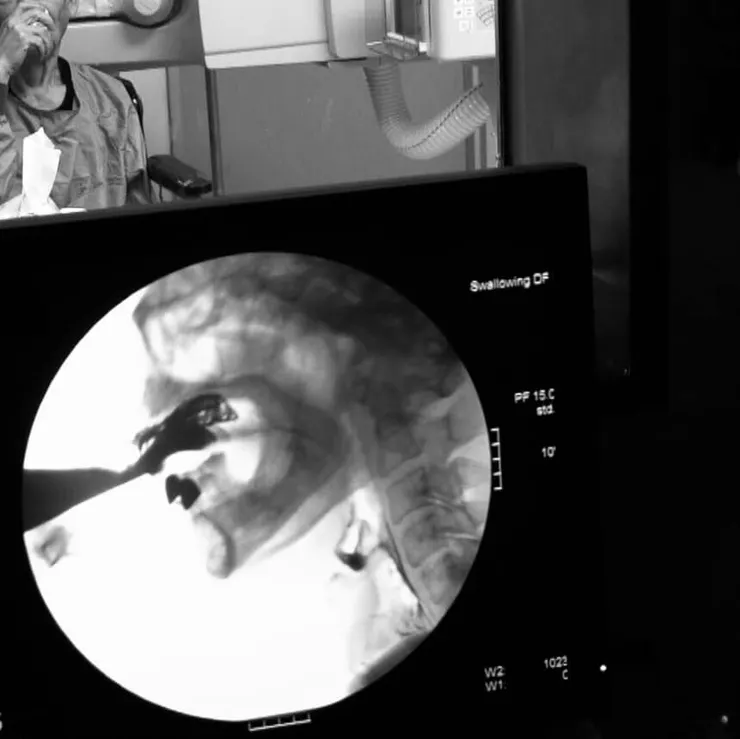

可以在精密的吞嚥攝影檢查中

在一秒的吞嚥過程切分出超過一百個吞嚥細節

找出當中導致吞嚥困難的關鍵點

就如照片中這位陳伯伯

目前只要喝水就會嗆到

檢查後發現陳伯伯的安全吞嚥質地

需要至少米漿濃稠度才行!!

團隊將依照這個結果

討論並提供安全的吞嚥方案